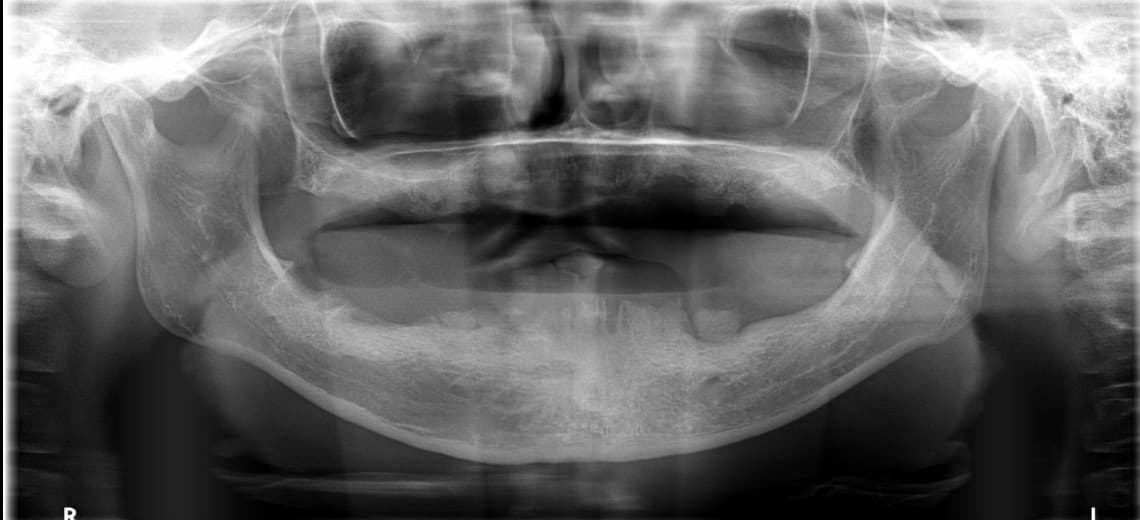

Suyak kam bo'lsa ham to'liq implant mumkinmi?

Ha, mumkin. Yonsei Ona Stomatologiyasi suyak ko'chirmasdan ham implant qilish texnologiyasiga ega. Raqamli yo'riqnoma tizimi bilan qolgan suyakning optimal joyini tahlil qilib, minimal suyak ko'chirish yoki suyak ko'chirmasdan jarrohlik o'tkaziladi. Boshqa stomatologiyalarda suyak yo'qligi sababli imkonsiz deb aytilgan ko'p bemorlar ham tashrif buyuradi.

Protezdan uzoq vaqt foydalandim, implantga almashtirishim mumkinmi?

Ha, almashtirishingiz mumkin. Protezdan uzoq vaqt foydalangan bo'lsangiz ham 3D CT bilan milka suyagi holatini aniq diagnostika qilib, implant imkoniyati aniqlanadi. Suyak so'rilgan bo'lsa ham raqamli yo'riqnoma texnologiyasi bilan qolgan suyakni maksimal darajada ishlatamiz, zarur bo'lsa minimal suyak ko'chirish bilan davom etamiz.